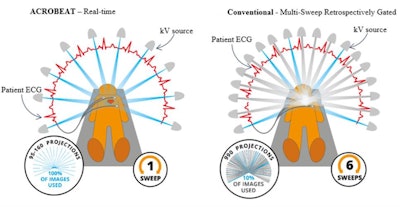

Left: Patient-connected imaging with ACROBEAT. The gantry trajectory and timing of the projection acquisition are adapted to the patient's ECG signal (red) as it evolves in real-time. Right: Conventional multisweep retrospectively ECG-gated acquisition. The gantry trajectory and timing of the projection acquisition are constant throughout the duration of the scan. Image courtesy of Reynolds et al, Phys Med Biol, 10.1088/1361-6560/ab03f4.

Left: Patient-connected imaging with ACROBEAT. The gantry trajectory and timing of the projection acquisition are adapted to the patient's ECG signal (red) as it evolves in real-time. Right: Conventional multisweep retrospectively ECG-gated acquisition. The gantry trajectory and timing of the projection acquisition are constant throughout the duration of the scan. Image courtesy of Reynolds et al, Phys Med Biol, 10.1088/1361-6560/ab03f4.The team examined acquisition windows of 30% to 40% and 60% to 70% through the cardiac cycle, representing optimal gating windows with minimal heart motion. They also investigated the 80% to 90% window, where large heart motion is observed, and a longer window spanning 60% to 80% of the cardiac cycle.